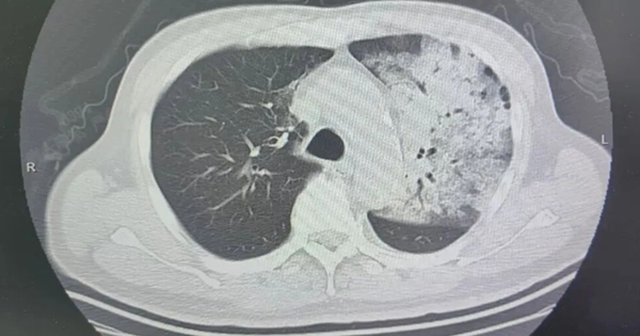

Sau khoảng một tuần điều trị tại bệnh viện địa phương, bệnh tình của ông đột ngột xấu đi. Bệnh nhân bắt đầu khó thở, rối loạn ý thức. K ết quả chụp CT cho thấy 2 phổi bị nhiễm trùng nặng, gần như “trắng xóa” . Dù đã được hỗ trợ thở máy nhưng tình trạng oxy máu vẫn không cải thiện.

Người đàn ông sốt 40 độ C, phổi gần như "trắng xóa", chỉ vài ngày đã suy đa tạng: Thủ phạm liên quan đến thói quen nhiều gia đình vẫn mắc- Ảnh 1.